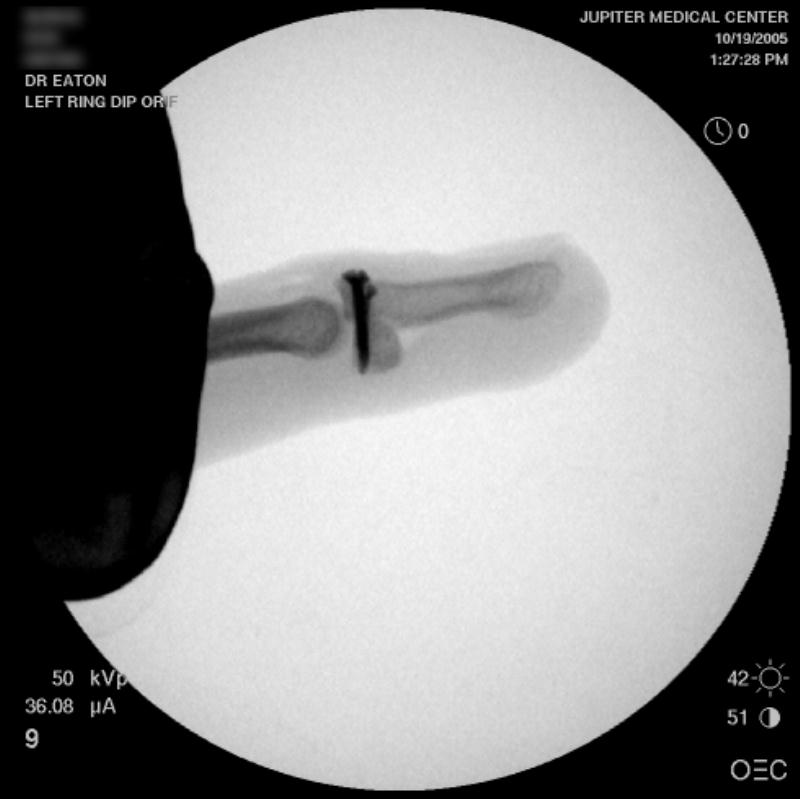

Finger Distal Interphalangeal Joint Fusion Surgery Performed by Dr Distal Interphalangeal Joint Replacement — the phalanges in each finger are separated by joints called interphalangeal or ip joints. People with arthritis may experience pain,. The ip joint closest to the mcp is called the. — the distal interphalangeal (dip) joint connects the bones at the tips of the fingers. Symptomatic distal interphalangeal (dip) joint arthritis is frequently treated by arthrodesis, though.. Distal Interphalangeal Joint Replacement.

From eatonhand.com